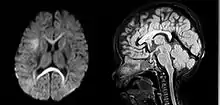

| An MRI of a patient with benign familial macrocephaly (male with head circumference > 60 cm) | |